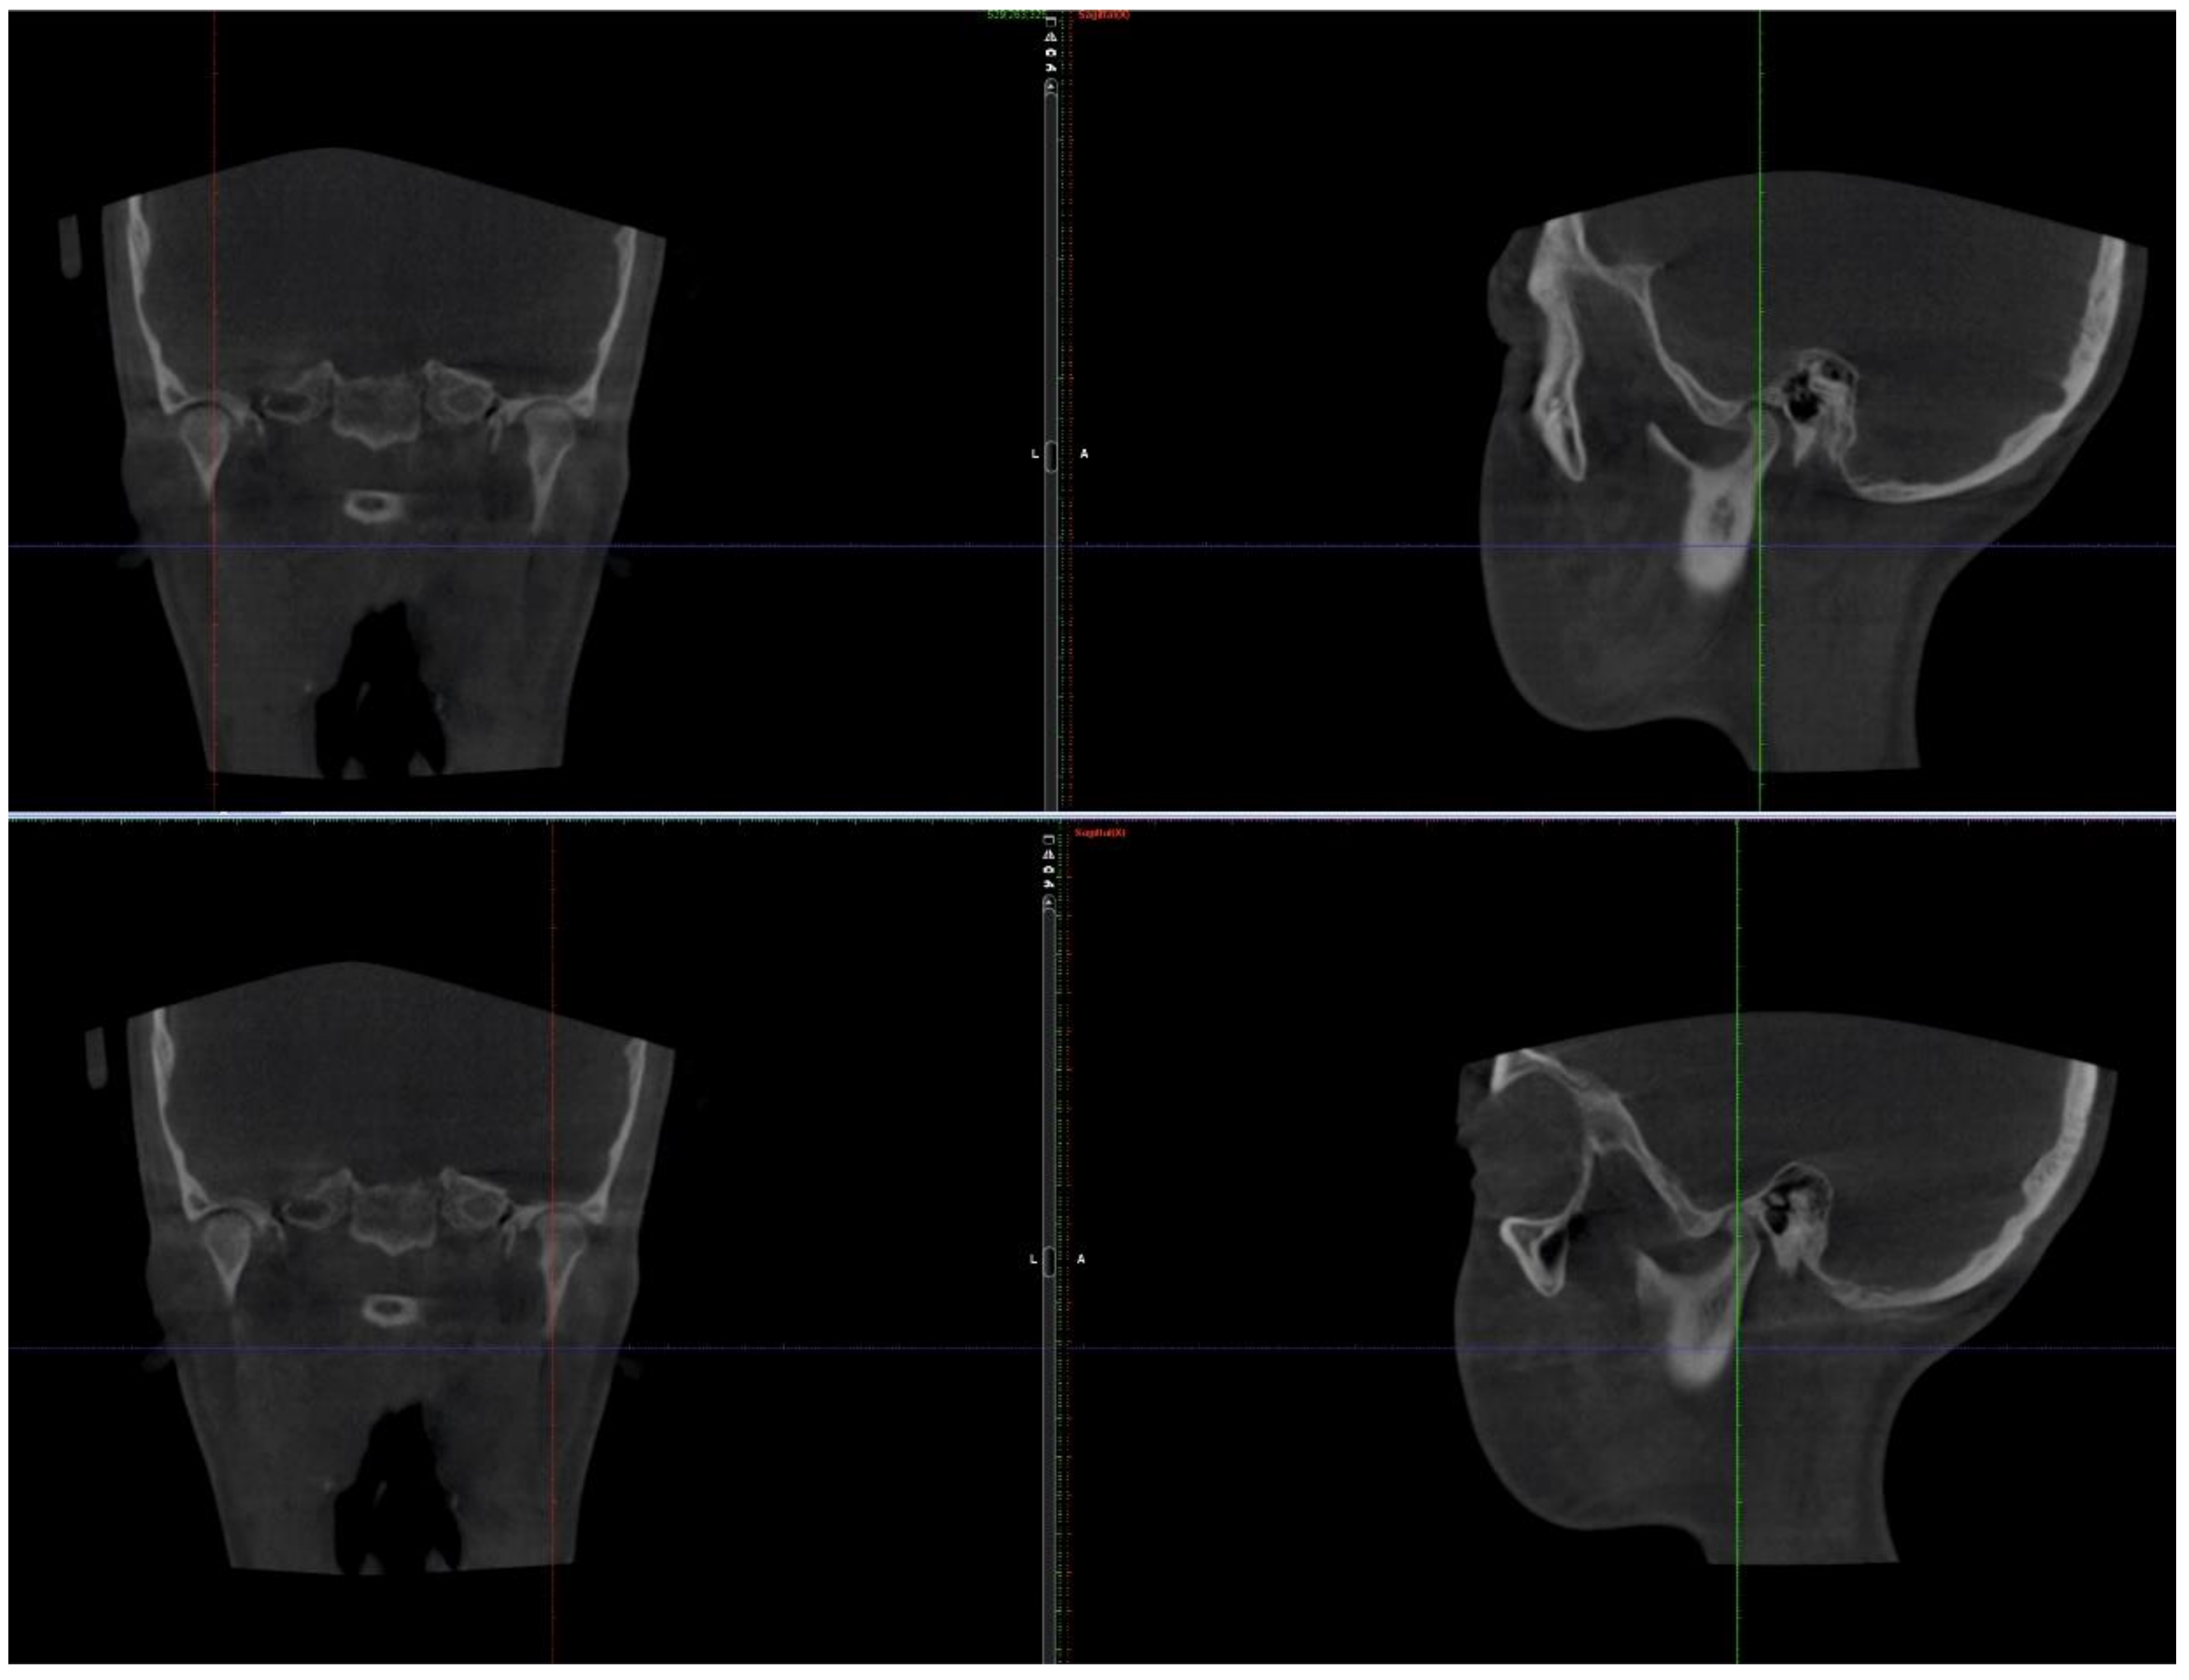

2.1. Initial Diagnosis and Initial Surgical Management

2.3.1. First Treatment Phase—2016—TMJ Splint Therapy

2.3.2. Second Phase of Treatment—2017—Bite-Blocks and Transpalatal Arch